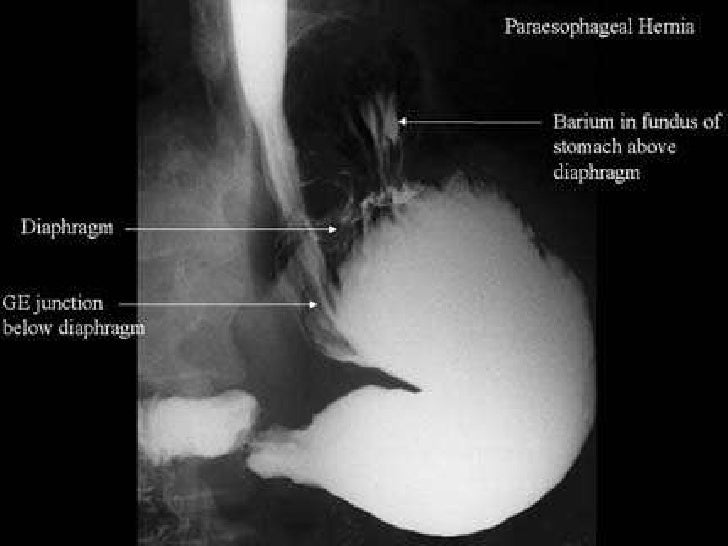

Медицинские исследования: КТ при грыже пищеводного отверстия